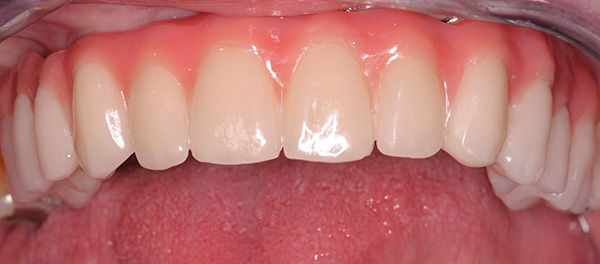

- Si ottiene un'alta estetica, poiché molta attenzione viene rimossa dalla formazione del contorno delle gengive attorno alla corona;

Le fotografie seguenti mostrano un esempio di impianto di un dente anteriore appena rimosso (che si è rotto da una lesione meccanica):

nota

In alcune situazioni, quando le condizioni del tessuto osseo lo consentono e l'impianto ha una fissazione primaria abbastanza buona, è possibile installare una corona in metallo-plastica economica per il periodo di osteointegrazione dell'impianto. Per i denti anteriori, questo è particolarmente importante, poiché consente di ripristinare l'estetica della dentatura in modalità express. Considerando che i denti anteriori non sono coinvolti nella masticazione del cibo, il carico sull'impianto sarà minimo.

La caratteristica più importante del metodo basale degli impianti dentali è la possibilità di protesi quasi istantanee. Vale a dire, letteralmente già 2-3 giorni dopo l'installazione degli impianti, le protesi fisse sono fisse. Sono realizzati in metallo-plastica e hanno una piccola base in plastica, la protesi è abbastanza leggera.La gomma artificiale, che in pratica non differisce nell'aspetto da quella naturale, consente di migliorare l'estetica della dentatura (si osserva spesso una lunga assenza di denti si verifica una subsidenza irregolare dell'osso con la gomma).